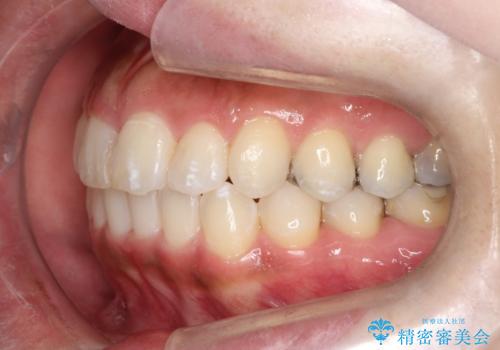

- 前歯のガタツキが気になると来院されました。

奥歯の噛み合わせは綺麗に噛んでいたため、前歯の叢生(でこぼこ)に集中して治療するように計画しました。

奥歯の噛み合わせは整っていたため、前歯の並びを美しく修正することに専念できました。